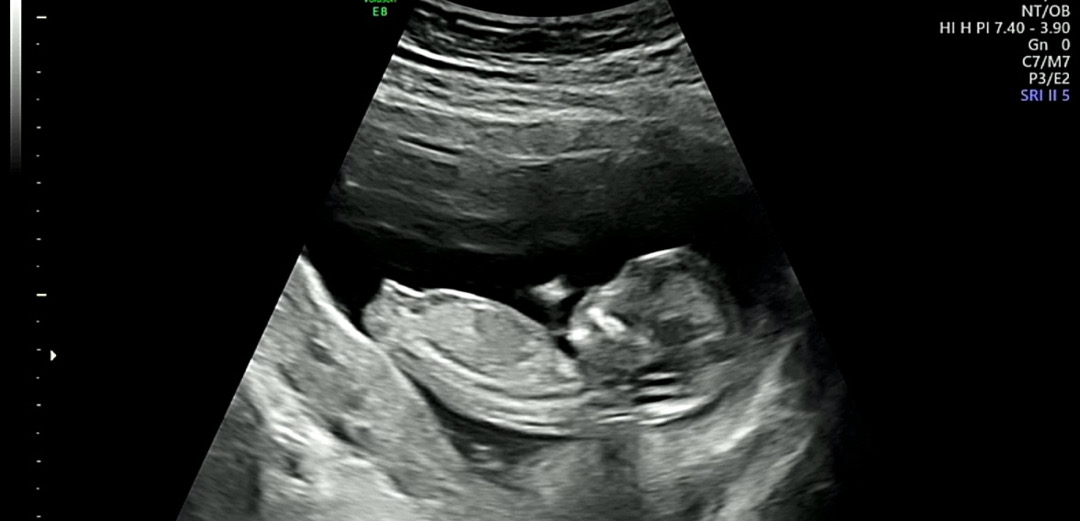

12주3일차 각도법 보이시나요???

오늘 보고 왔는데 너무 헷갈려요ㅠㅠ 혹시 보이시나요????

척추랑 거의 나란한것이 딸인거같아 보여요~ 옆으로 예쁘게 잘 누웠네요ㅜ 저는 등만보여줘서 각도가 잘 안보이더라구요ㅠㅠ

각도는 딸같아요!